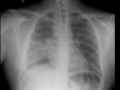

Miliary Tuberculosis (TB) on X-ray

Patient with miliary tuberculosis. Chest radiographs demonstrate diffuse micronodular infiltrates compatible with miliary TB. There is also an alveolar infiltrate with cavitation in the superior segment of the right lower lobe. A partially loculated right pleural effusion is also noted.